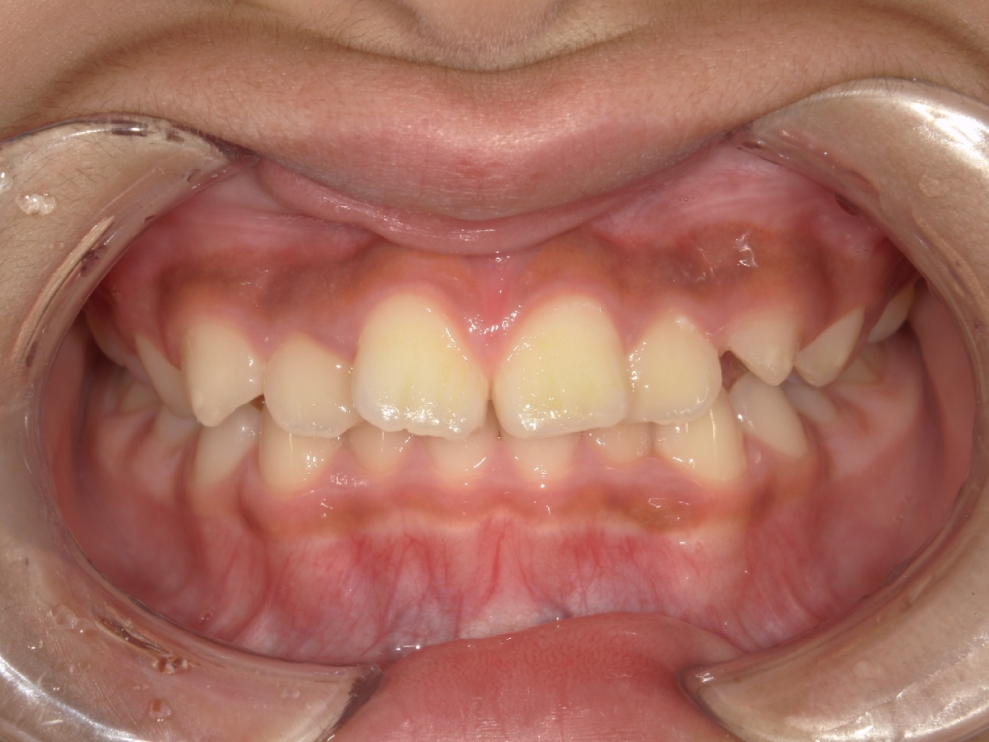

BEFORE

スタート時9歳の患者さまで、主訴は上下前歯のガタつきでした。早期に歯並びを整えたいとの思いからご相談に来院されました。

成長期であることを踏まえ、段階的な治療計画を立てました。まずプレオルソを1年1ヶ月使用し、口腔周囲筋や歯列のバランスを整えたうえで、その後、マウスピース矯正インビザライン・ファーストにて矯正治療を行い、さらに1年8ヶ月かけて歯並びを整えています。